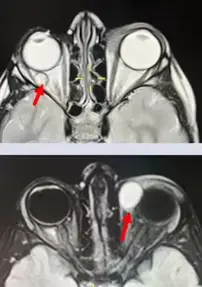

Рисунок 19. КТ и МРТ подтверждают объемные образования правой и левой орбиты.КТ и МРТ подтверждают объемные образования правой и левой орбиты (см. рис. 19).